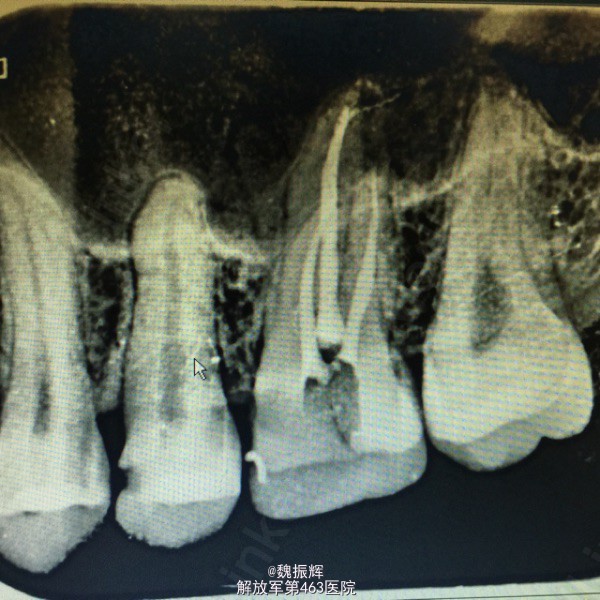

患者男性,23岁,左上后牙食物嵌塞痛数周,近日有自发痛夜间痛表现。影响进食,睡眠。来院就诊。

26的近中龋坏,探(+),冷(+),叩(-),X线示龋坏近髓达髓角。

诊断:26牙髓炎 处理:局麻下,26调合,去腐,开髓,拔髓,疏通根管,根管预备,根管冲洗,行一次性根管充填,氧化锌暂封。观察准备嵌体修复。